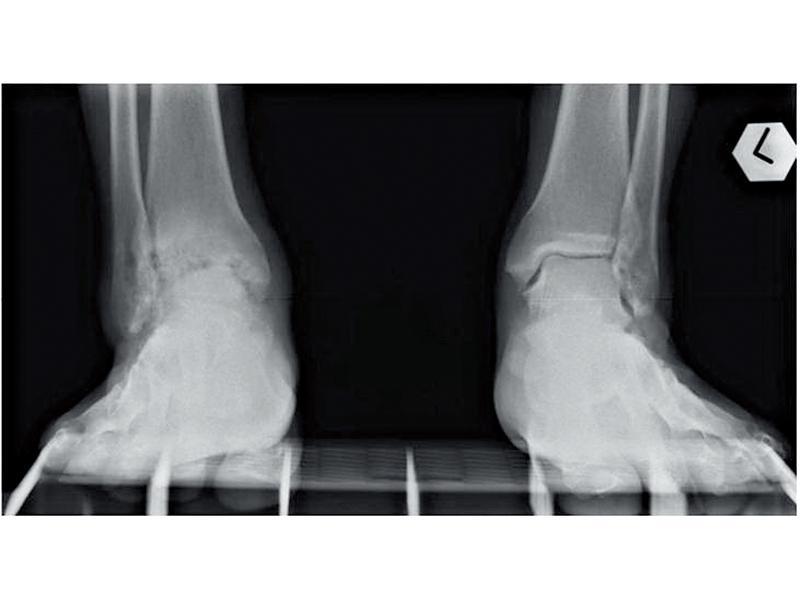

全踝關節置換術6周復元

要診斷是否患有腳踝關節炎,醫生會先為患者進行臨床檢查,觀察患者的步姿及檢查疼痛的關節;醫生又會為患者進行X光檢查,檢測患者的腳踝關節空間是否較窄或出現改變;若有需要時,患者可能要接受骨骼掃描、電腦斷層掃描或磁力共振,檢視骨骼及軟組織。

在治療腳踝關節炎方面,楊揚醫生又稱:「現時主要有兩個治療方法,包括是踝關節融合術及全踝關節置換術,前者的穩定性較高,相反流動性就較低,復元時間需要三至六個月,價錢較便宜,因此較適合長者或較少活動的人士;而後者的穩定性稍低,但靈活性較高,復元時間只需六個星期,所以較適合年輕及多活動的患者。」